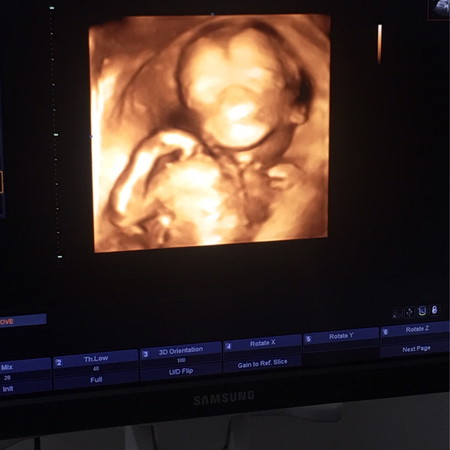

น้องเพิ่งจะ5เดือนเอง สายสะดือพันคอ หมอบอกว่าน้ำคร่ำเยอะอยู่เดี๋ยวก็คลายออกเอง แต่จะให้คนเป็นเเม่ไม่คิดมากไม่ได้หรอก กลัวจะพันหนักกว่าเก่าอีก???